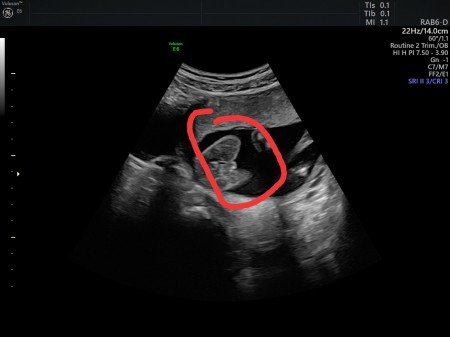

Kızlaaarrr.. Hatırlayan olur belkı bırkac hafta once bır erker bır kız dediler kafam karısık detaylı ultrasonu beklıyorum demiştim detaylı da ben sormadan doktor kız geliyor dedi coook mutluyuz Cokk Rabbım isteyen herkese nasip etsin.. İnsşAllah sonradan yıne bırı cıkıp erkek demez :)))

Gebelik haftası 20+4

Hayır ne güzl popoyu dönmüş resmen bakın cinsiyeti e demiş kurban olurum ya saglıkla gelsin prenses

Kiz bu bildigin kizzzzz masallah açmış gostermiste <3

Eveeeet alın bakın yeter dedi sanırım :)))